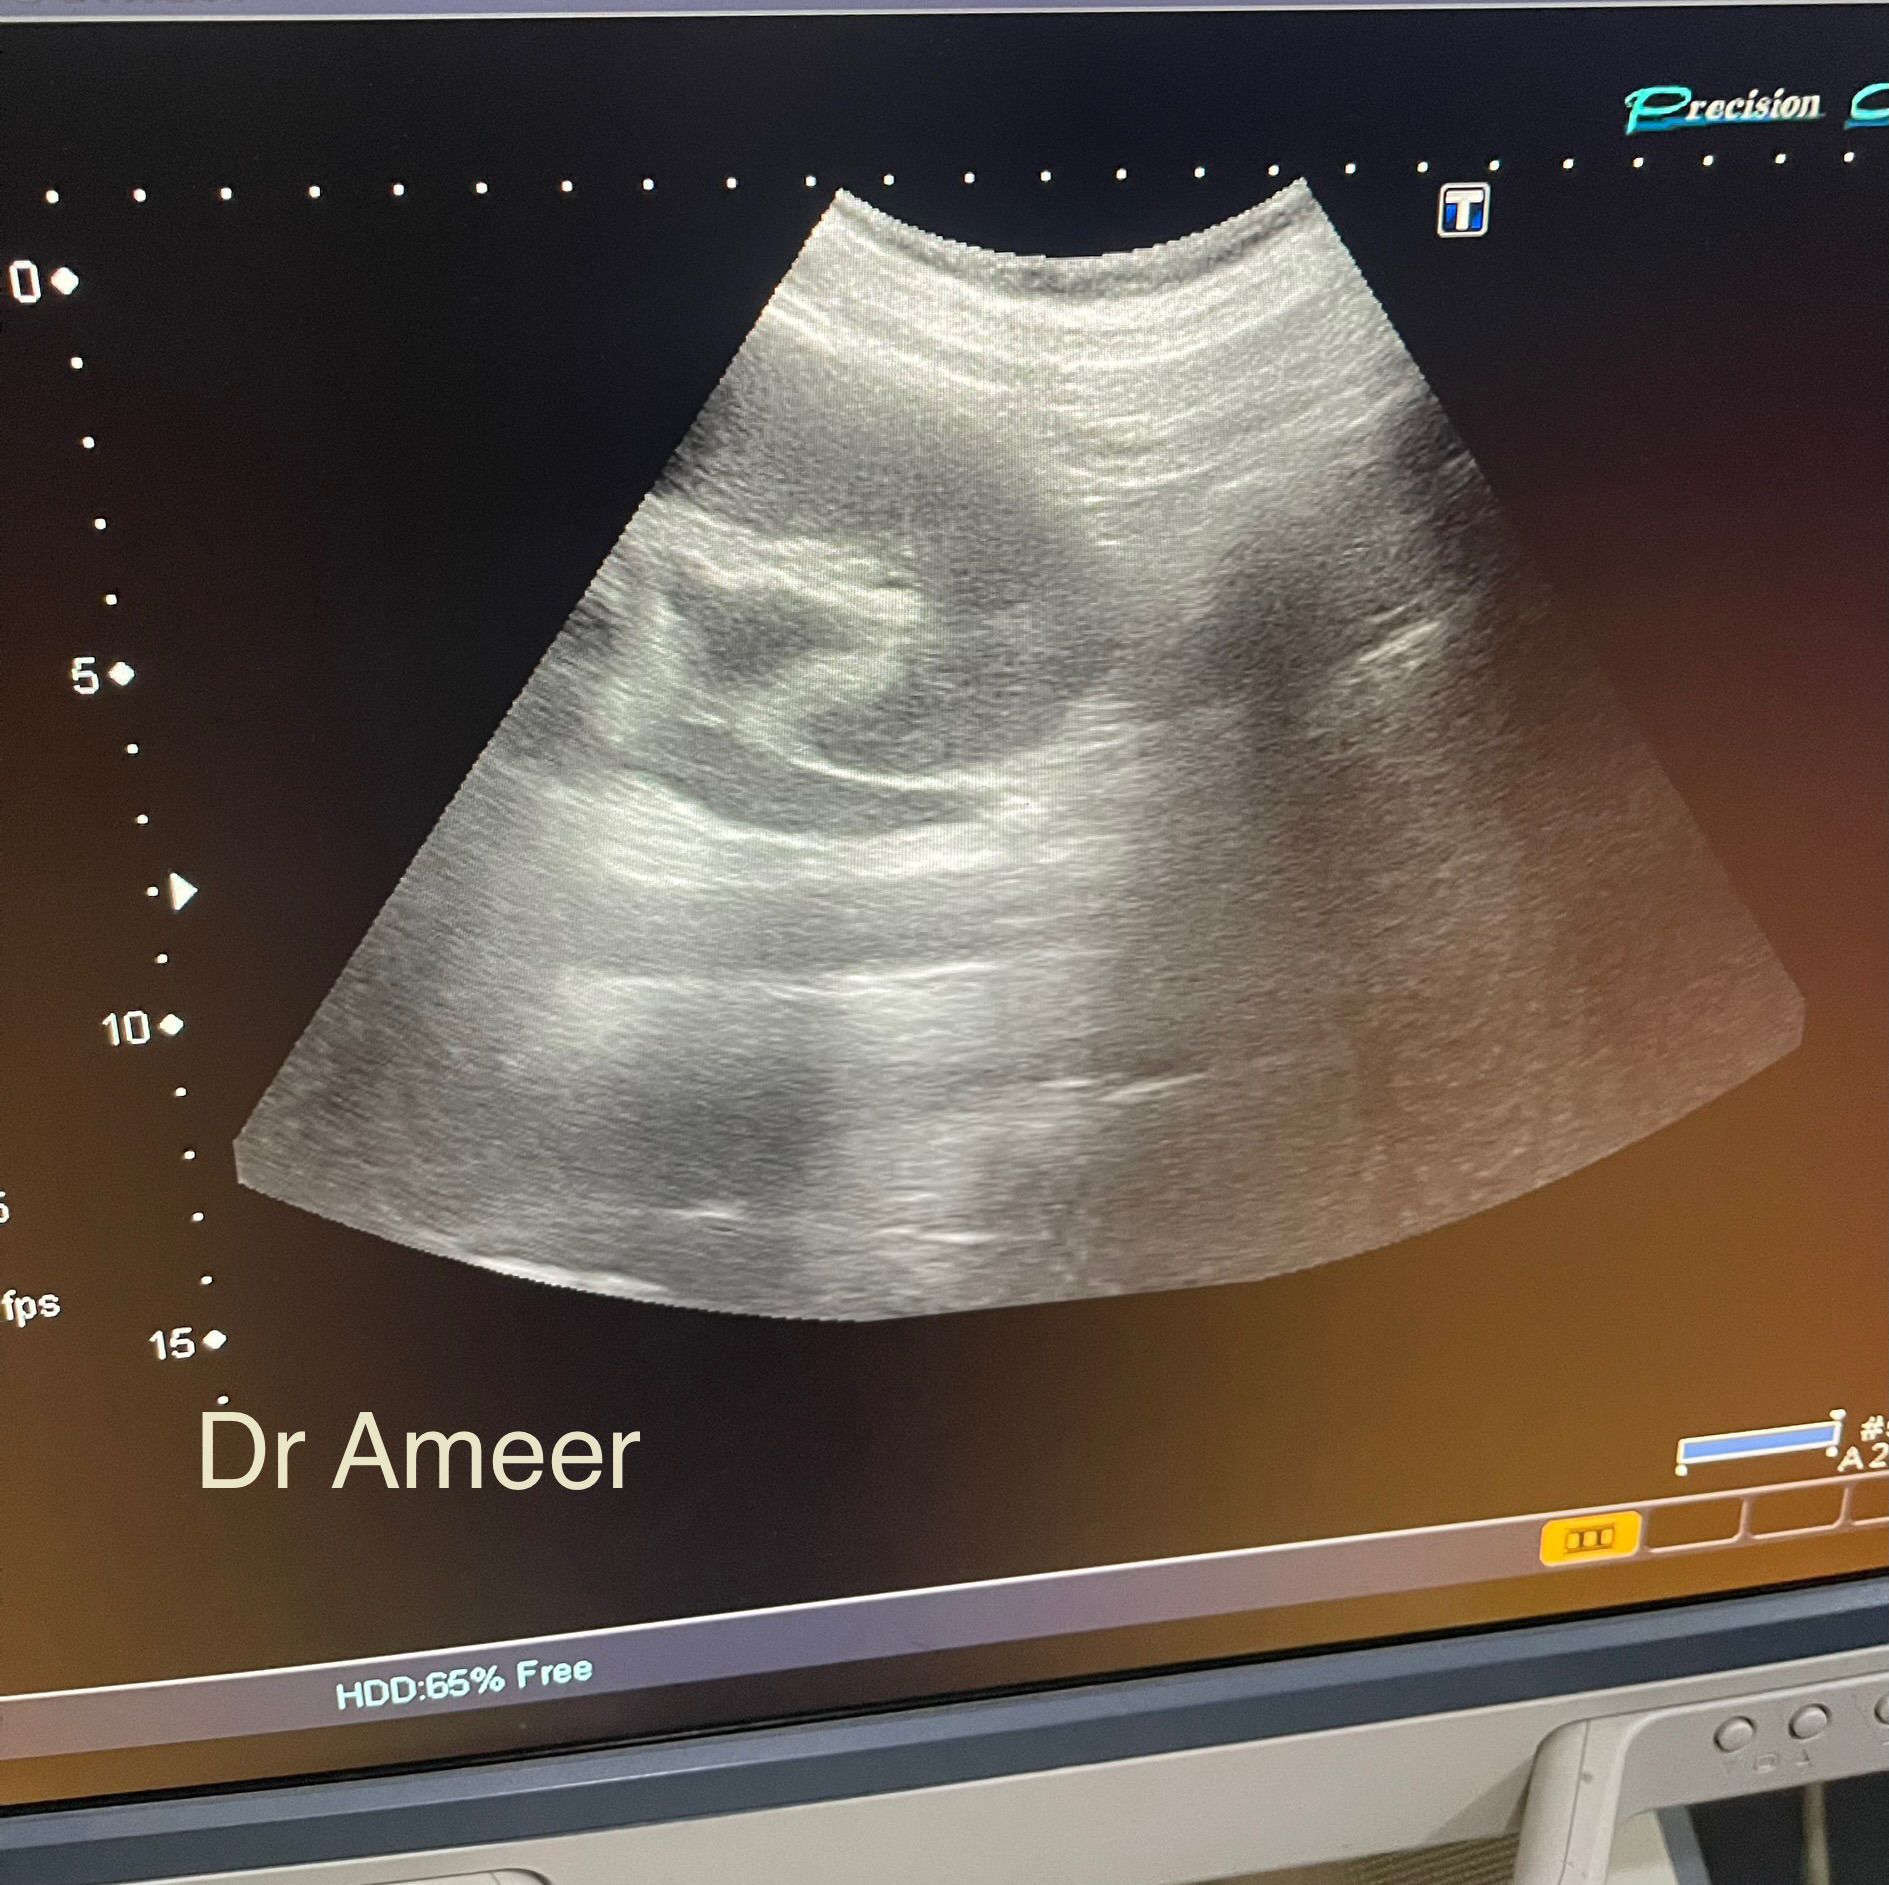

Ultrasound KUB

Patient presented in ER with left sided flank pain severe in intensity radiating to the groin. Ultrasound was done. Can you appreciate findings in the image shared?